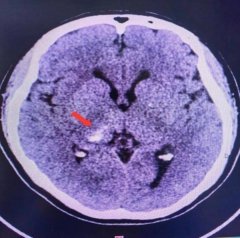

脑出血